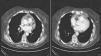

The case of a 76-year-old woman who presented in the emergency room with fever (38°C) is reported. She had had episodes of fever and pain in the pectoral girdle radiating to the cervical region over the previous 2 months. On one occasion, she had received oral corticosteroids in tapering schedule, with improvement. Physical examination revealed a systolic murmur in the aortic region and absent breath sounds in the base of the left lung. Clinical laboratory tests showed C-reactive protein 25.5mg/dl and a small left pleural effusion was observed on the chest X-ray. The initial diagnosis was pneumonia with parapneumonic pleural effusion and the patient was hospitalized with empiric antibiotic therapy. Despite this, her fever persisted and further examinations were performed. The immunological study revealed positive antinuclear antibodies in a speckled pattern. Tumor marker analysis showed elevated CA-125 levels. The chest-abdominal computed tomography showed a small left pleural effusion and minimal pericardial effusion (Fig. 1). After consultation with the rheumatologist, a diagnosis of RPM with serosal involvement was made and treatment with prednisone (starting dose: 15mg/day) was initiated. Subsequent clinical course was favorable with resolution of fever and pleural effusion. Three months after discharge the patient remained asymptomatic, so the corticosteroid doses were progressively reduced until discontinuation. The patient has since remained asymptomatic, with no new outbreaks of RPM over a 2-year follow-up period.